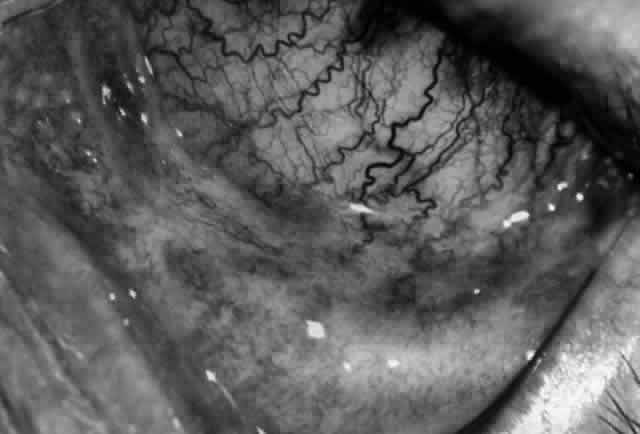

Clinically, the ocular disease in cicatricial pemphigoid (OCP) may present unilaterally in the form of a chronic, recurrent catarrhal conjunctivitis, but it eventually becomes bilateral. Subepithelial fibrosis is characteristic of stage 1 of OCP (Fig. 7). Stage 2 shows fornix foreshortening (Fig. 8), and symblepharon formation is the hallmark of stage 3 (Fig. 9). Stage 4, end-stage disease, is characterized by ankyloblepharon and surface keratinization (Fig. 10). Obstruction of the lacrimal ductules and meibomian gland ducts eventually produces an unstable tear film and progressive sicca syndrome, but it is to be emphasized that OCP is not a dry-eye syndrome until late in the disease course.20 Trichiasis and entropion occur because of the subepithelial fibrosis, with eventual keratopathy, corneal neovascularization, and corneal ulceration and scarring.20

Fig. 9. Stage 3 of an eye affected by cicatricial pemphigoid. The conjunctival “shrinkage” continued and a frank symblepharon developed.